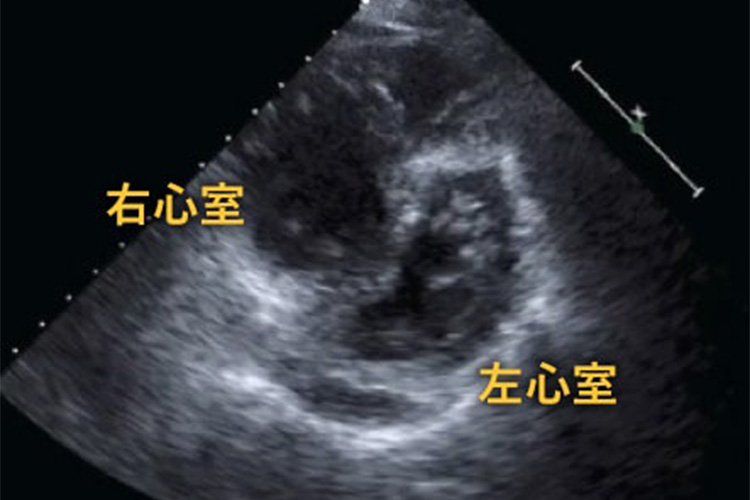

心臓超音波検査のイメージ

心臓超音波検査では、心臓の弁の形や動き、心筋の厚みや収縮などを評価します。肺血栓塞栓症が起きると右心室の圧力が高まり、左心室が圧排されて見られることがあります。

また、下肢静脈超音波検査では静脈の血流有無を見たり、軽く圧迫しながら検査することで血栓の有無を確認します。